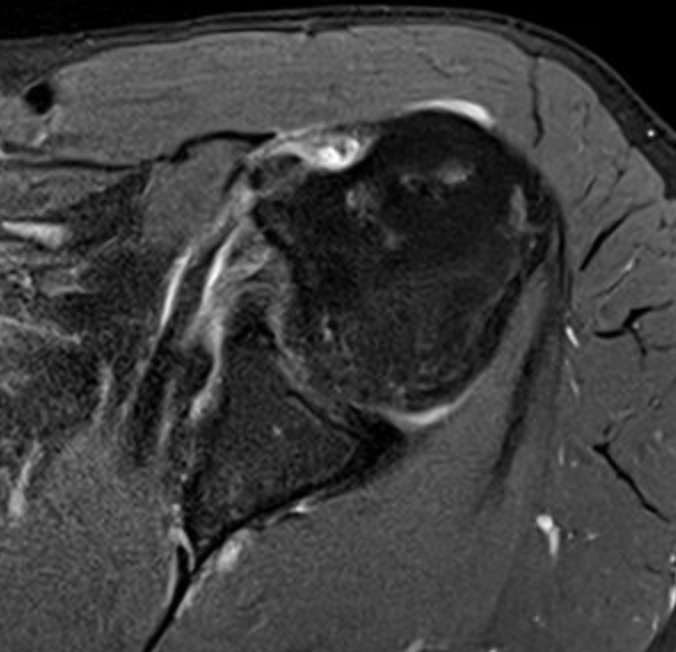

MRI

Medial Subluxation

Medial subluxation with subscapularis tear